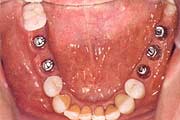

Zahnloser Kiefer

Viele Prothesenträger klagen über den schlechten Sitz und

schmerzhaften Druckstellen. Haftmittel oder mechanische Hilfen lösen

diese Probleme nicht dauerhaft und zufriedenstellend.

Implantate können Abhilfe schaffen, abhängig von Ihren Voraussetzungen und Wünschen. So kann der Tragekomfort mit der Anzahl der Implantate erheblich gesteigert werden, bis hin zu einer rein auf künstlichen Wurzeln getragenen Prothese.

Beim CAMLOG(r) -System stehen unterschiedliche Möglichkeiten für Sie zur Verfügung:

Druck-Knopf-Verankerung - einfach und zuverlässig

![]() |